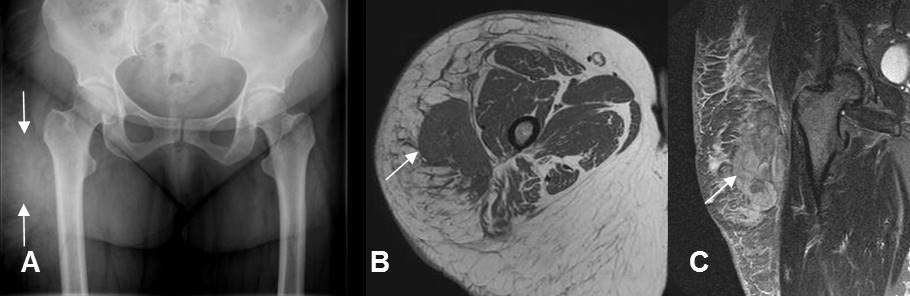

Fig 151. Hematoma muscular subagudo.

A: RM coronal en T1. Colección heterogénea, con áreas hiperintensas por evolución subaguda, en el músculo vasto externo.

B: RM axial en T2 y C: RM sagital en STIR. Colección intramuscular, definida e hiperintensa.